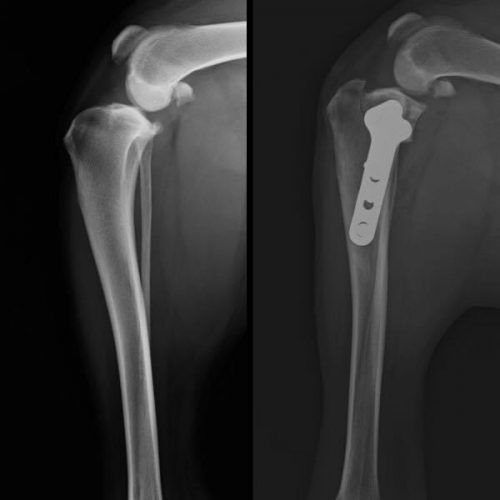

ORTOPEDIA